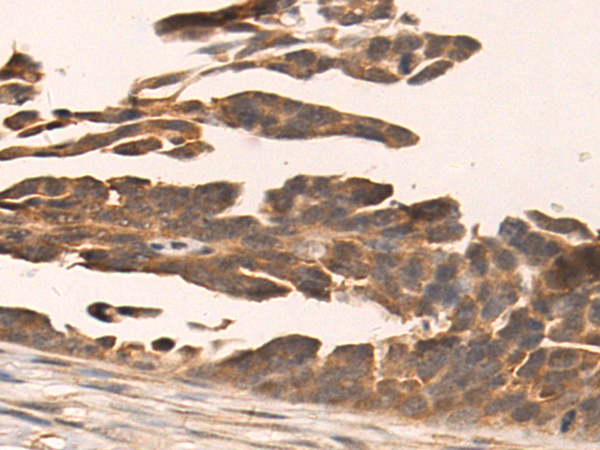

分类: 科研抗体货号: P07389别名: MUM1; LSIRF; SHEP8; NF-EM5应用: IHC反应种属: Human, Mouse

分类: 科研抗体货号: P07404别名: UKLF应用: IHC反应种属: Human

分类: 科研抗体货号: P07388别名:应用: IHC反应种属: Human, Mouse

分类: 科研抗体货号: P07419别名:应用: IHC反应种属: Human, Mouse

分类: 科研抗体货号: P07385别名: GT; CD61; GP3A; BDPLT2; GPIIIa; BDPLT16应用: WB,IHC反应种属: Human, Mouse, Rat

分类: 科研抗体货号: P07417别名: LEF-1; TCF10; TCF7L3; TCF1ALPHA应用: IHC反应种属: Human, Mouse, Rat

分类: 科研抗体货号: P07402别名: JNK; JNK1; PRKM8; SAPK1; JNK-46; JNK1A2; SAPK1c; JNK21B1/2应用: WB,IHC反应种属: Human, Mouse, Rat

分类: 科研抗体货号: P07384别名: EDF; FRP应用: WB,IHC反应种属: Human, Mouse, Rat